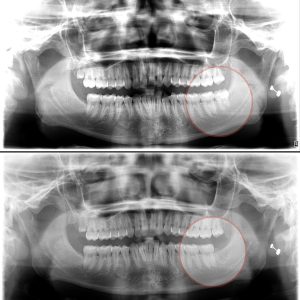

Răng khôn (hay còn gọi là răng số 8) là những chiếc răng cuối cùng trong hàm, thường mọc trong độ tuổi từ 17 đến 25. Việc mọc răng khôn đôi khi có thể gây ra nhiều vấn đề và biến chứng cho sức khỏe răng miệng.

1. Trường hợp KHÔNG cần nhổ răng khôn: 2. Trường hợp NÊN nhổ răng khôn: Khi hàm không đủ chỗ cho răng khôn mọc lên...